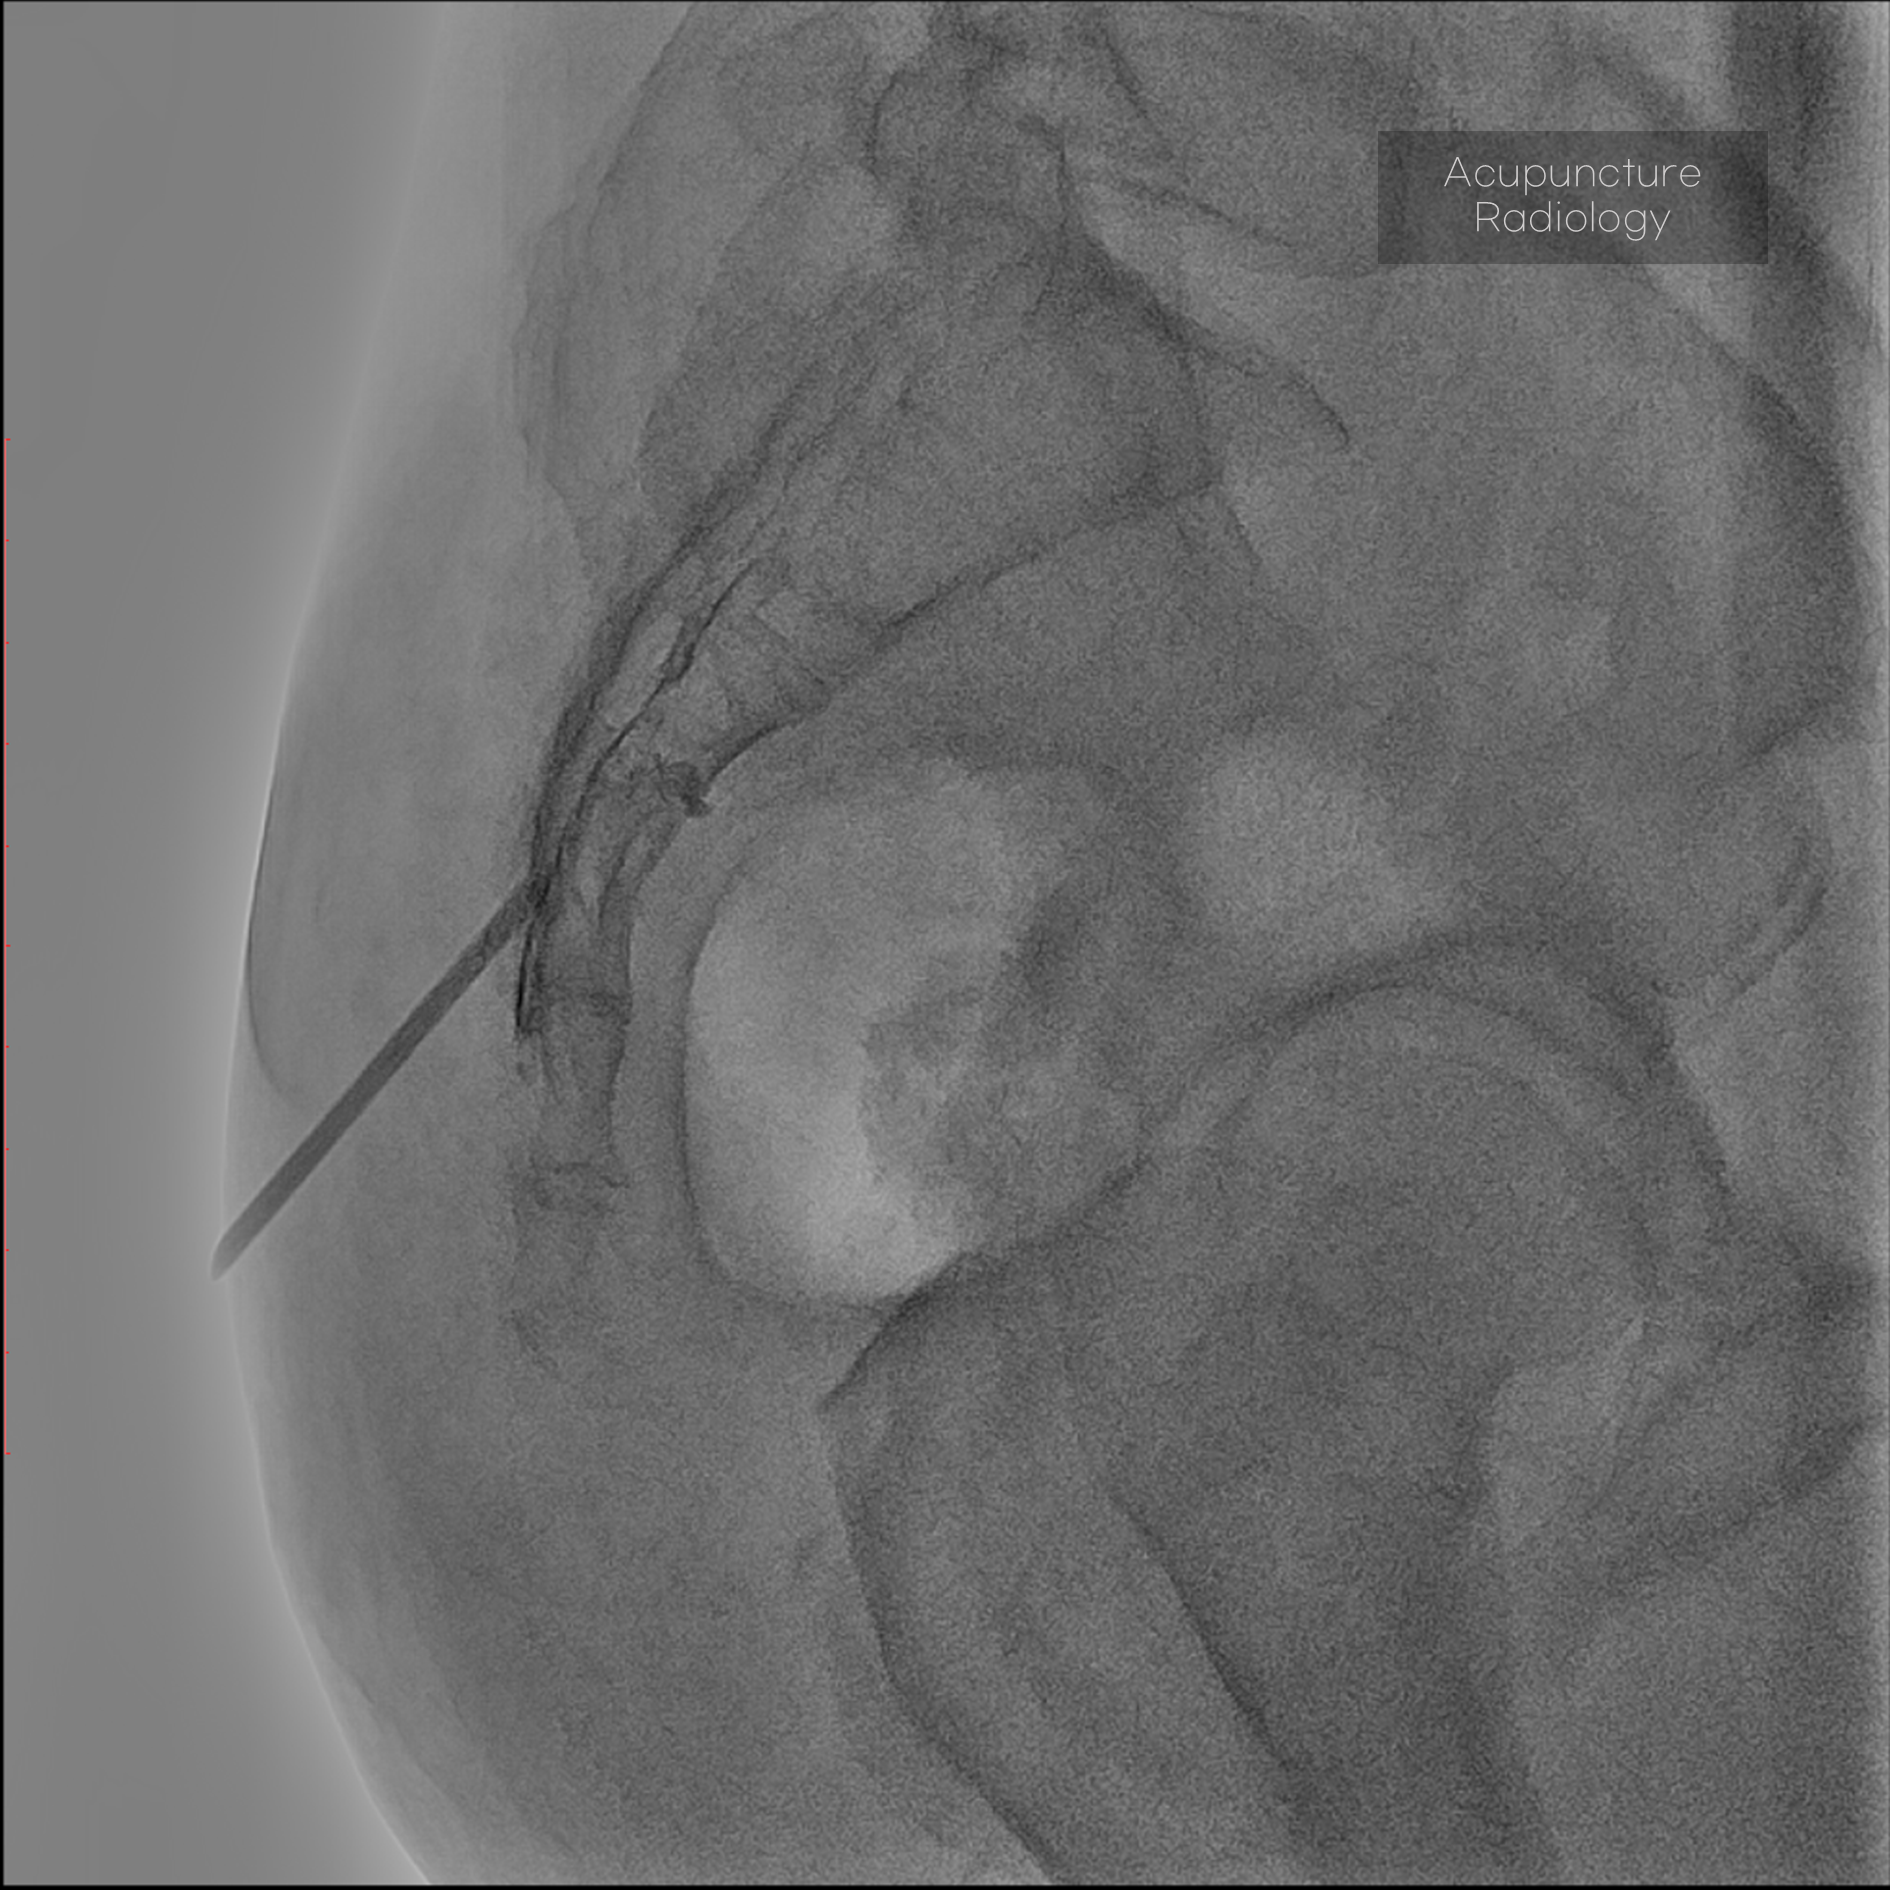

Editorial/Editor's Pick 경막외 유착박리술, Epidural Neuroplasty by Pharmacopuncture Research Lab 2026. 1. 3. 공유하기 게시글 관리 Acupuncture Radiology 관련글 MRI 요양급여의 적용기준 및 방법에 관한 세부사항 MRI 요양급여의 적용기준 및 방법에 관한 세부사항 [신구대조표] Association of AI‑determinedKellgren–Lawrence grade Portable X-ray